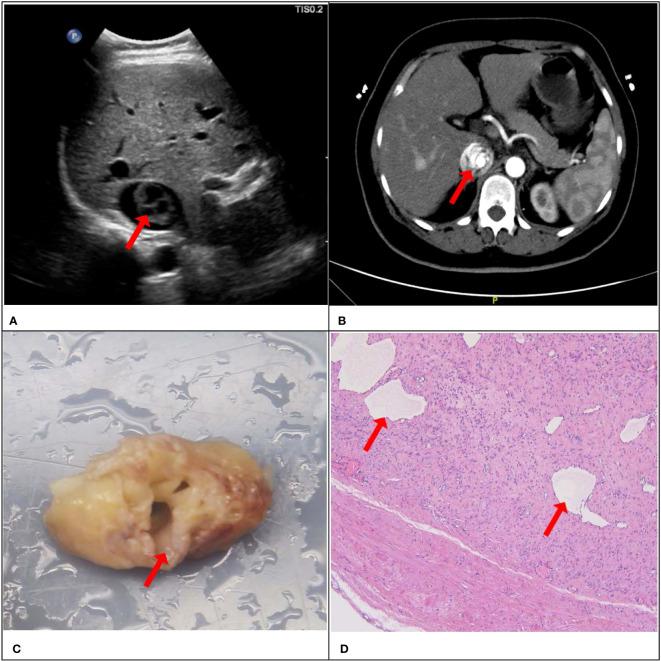

A total of 284 patients diagnosed with IVC-occupying lesions were included in the study. The lesion types comprised of IVL (n=67, 23.6%), IVC thrombus (n=135, 47.5%), tumor thrombus of renal carcinoma involving the IVC (n=35, 12.4%), tumor thrombus of liver carcinoma involving the IVC (n=24, 8.5%), leiomyosarcoma of the IVC (n=14, 4.9%), and tumor thrombus of adrenocortical adenocarcinoma (n=9, 4.1%). The presence of "sieve hole" and "multi-track" signs was observed in 20 IVL lesions under the grey-scale modality, while both signs were absent in the non-IVL group (<0.01). The study found no statistically significant differences in the presentation of "sieve hole" and "multi-track" signs under the grey-scale and color Doppler modalities in cases of intravascular lithotripsy (IVL) (>0.05). Using these two signs as diagnostic criteria for IVL, the sensitivity, specificity, positive predictive value (PPV), negative predictive value (NPV), miss rate, misdiagnosis rate, and accuracy were determined to be 29.9%, 100%, 100%, 82.2%, 70.1%, 0, and 83.5%, respectively (AUC ROC=0.649; 95%CI: 0.537-0.761).

IVL exhibits distinct ultrasound presentations, including "sieve hole" and "multi-track" signs, which demonstrate high specificity and accuracy as diagnostic indicators. Furthermore, these signs are corroborated by pathological evidence and effectively distinguish IVL from other lesions occupying the IVC.